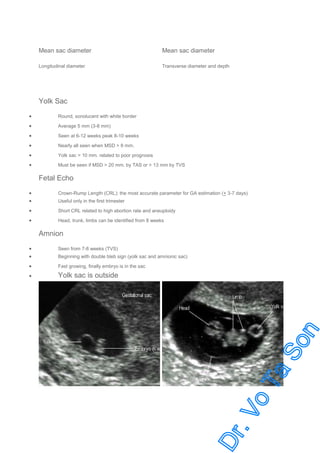

Yolk Sac

•

Round, sonolucent with white border

Average 5 mm (3-8 mm)

Seen at 6-12 weeks peak 8-10 weeks

Nearly all seen when MSD > 8 mm.

Yolk sac > 10 mm. related to poor prognosis

Must be seen if MSD > 20 mm. by TAS or > 13 mm by TVS

Fetal Echo

Crown-Rump Length (CRL): the most accurate parameter for GA estimation (+ 3-7 days)

Short CRL related to high abortion rate and aneuploidy

Head, trunk, limbs can be identified from 8 weeks

Useful only in the first trimester

Amnion

Seen from 7-8 weeks (TVS)

Fast growing, finally embryo is in the sac

Yolk sac is outside

Beginning with double bleb sign (yolk sac and amnionic sac)